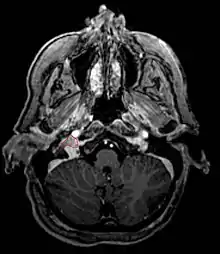

Glomus Jugulare

- Commonly arise from the paraganglia of the jugular bulb

- Typically invade the tympanic cavity and jugular foramen

- Can extensively invade petroclival region